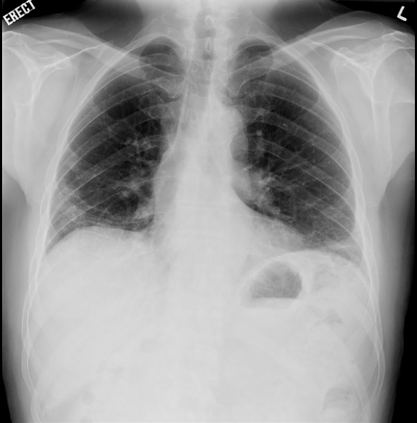

In this study, we aim to initiate the development of Radiology Foundation Model, termed as RadFM.We consider the construction of foundational models from the perspectives of data, model design, and evaluation thoroughly. Our contribution can be concluded as follows: (i), we construct a large-scale Medical Multi-modal Dataset, MedMD, consisting of 16M 2D and 3D medical scans. To the best of our knowledge, this is the first multi-modal dataset containing 3D medical scans. (ii), We propose an architecture that enables visually conditioned generative pre-training, allowing for the integration of text input interleaved with 2D or 3D medical scans to generate response for diverse radiologic tasks. The model was initially pre-trained on MedMD and subsequently domain-specific fine-tuned on RadMD, a radiologic cleaned version of MedMD, containing 3M radiologic visual-language pairs. (iii), we propose a new evaluation benchmark that comprises five tasks, aiming to comprehensively assess the capability of foundation models in handling practical clinical problems. Our experimental results confirm that RadFM significantly outperforms existing multi-modal foundation models. The codes, data, and model checkpoint will all be made publicly available to promote further research and development in the field.